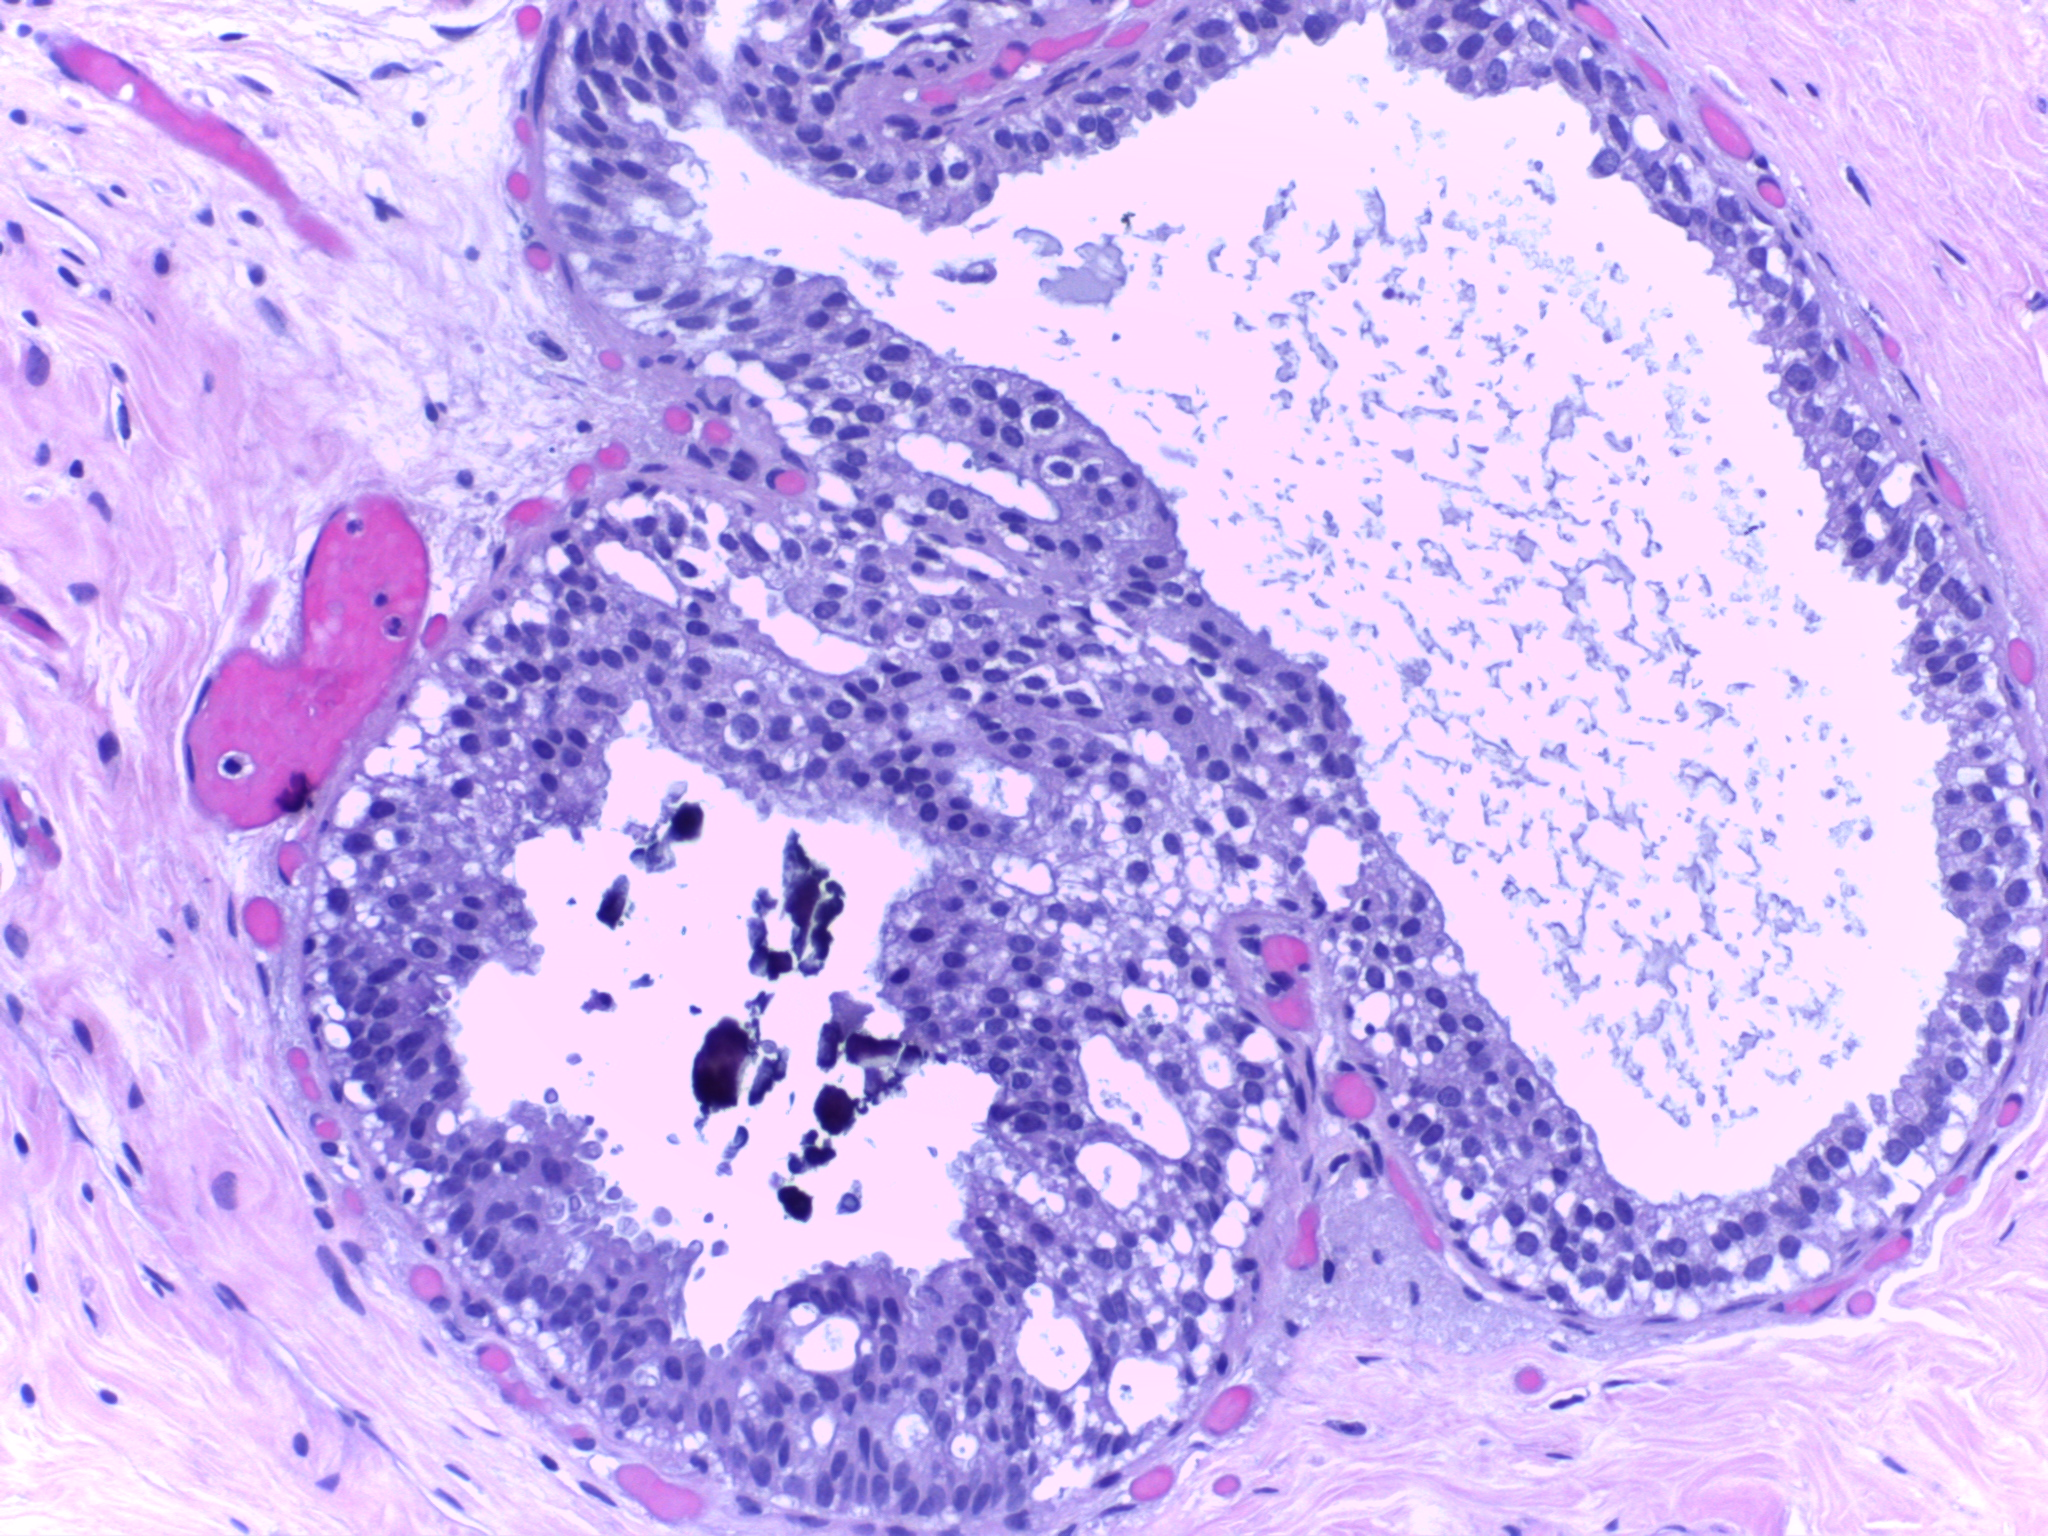

Figures 2 shows representative example outputs from CycleGAN, included solely to demonstrate domain adaptation feasibility between fluorescence microscopy and the H&E domain.